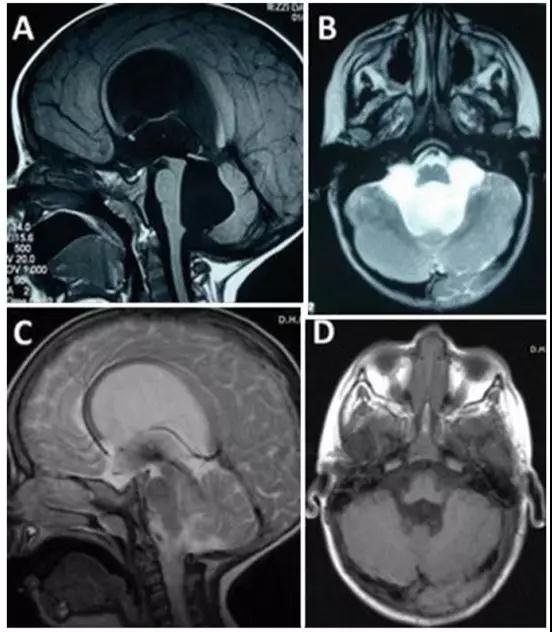

Concezio Di Rocco教授作为国际神经外科联合会基金小儿脑积水项目负责人,在脑积水手术方面经验丰富。在一份报告中,教授为一名因四脑室出口狭窄导致脑积水,合并小脑功能异常共济失调的3岁大的小男孩进行内镜下三脑室造口术,成功控制了脑积水的产生,手术过后小男孩症状迅速消退,预后效果好。

由于四脑室出口狭窄引起的脑积水小脑功能障碍,患有脑积水的3岁男孩。A、B为其术前影像,C、D显示内镜下三脑室造口术成功控制脑积水,术前症状迅速消退。